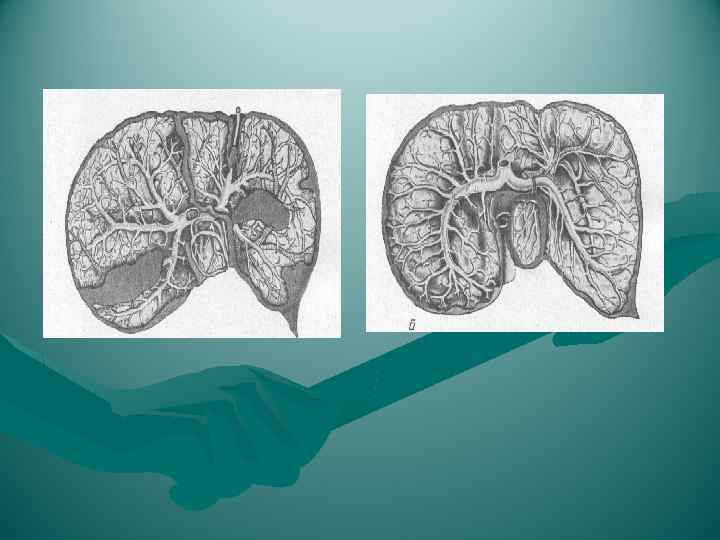

ОСОБЕННОСТИ КРОВОСНАБЖЕНИЯ ПЕЧЕНИ 1. Наличие двух венозных систем - портальной (портальные ворота печени) и кавальной (кавальные ворота печени) 2. Несовпадение хода сосудов двух систем. Ветви печеночных вен (v. v. hepaticae) не следуют ретроградно по пути печеночных артерий - проходят между ними и веерообразно сходятся в точке, ориентированной к v. cava inferior (кавальные ворота) 3. Наличие двух приносящих кровеносных сосудов - a. hepatica propria и v. portae (портальные ворота) 4. Слабое развитие внутрипеченочных анастомозов возможность некроза участка печени при перевязке ветви внепеченочной артерии

ОСОБЕННОСТИ КРОВОСНАБЖЕНИЯ ПЕЧЕНИ 1. Наличие двух венозных систем - портальной (портальные ворота печени) и кавальной (кавальные ворота печени) 2. Несовпадение хода сосудов двух систем. Ветви печеночных вен (v. v. hepaticae) не следуют ретроградно по пути печеночных артерий - проходят между ними и веерообразно сходятся в точке, ориентированной к v. cava inferior (кавальные ворота) 3. Наличие двух приносящих кровеносных сосудов - a. hepatica propria и v. portae (портальные ворота) 4. Слабое развитие внутрипеченочных анастомозов возможность некроза участка печени при перевязке ветви внепеченочной артерии

Кровь к печени поступает по двум системам: по воротной вене ( 70%) и по печеночной артерии (30%). Величина кровотока - 84 г на 100 г органа в минуту. Площадь поперечного сечения капилляров 400 м 2. Кровоток по воротной вене - 1, 5 л/м.

Кровь к печени поступает по двум системам: по воротной вене ( 70%) и по печеночной артерии (30%). Величина кровотока - 84 г на 100 г органа в минуту. Площадь поперечного сечения капилляров 400 м 2. Кровоток по воротной вене - 1, 5 л/м.

Отток по печеночным венам, их может быть от 4 до 8.

Отток по печеночным венам, их может быть от 4 до 8.